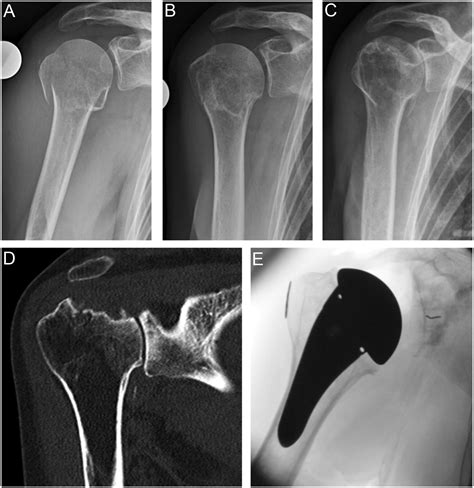

Classification of Proximal Humerus Fractures

Proximal humerus fractures are classified based on the location and pattern of the fracture. The most common classification systems include:

• Neer Classification: This system categorizes fractures based on the number of parts involved (one, two, three, or four parts).

• AO/OTA Classification: This system uses a more detailed coding system to describe the fracture pattern and severity.

Understanding the classification of the fracture helps healthcare providers determine the appropriate treatment plan.

For more severe fractures, surgery may be necessary to realign the bone and promote healing. Surgical options include:

• Open Reduction and Internal Fixation (ORIF): A procedure where the fracture is surgically realigned and stabilized using plates, screws, or pins.

• Hemiarthroplasty: Replacement of the humeral head with a prosthetic component, often used in older adults with severe fractures.

• Reverse Total Shoulder Arthroplasty: A more complex procedure where both the humeral head and the glenoid (socket) are replaced, providing better stability and function.